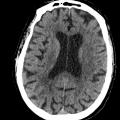

Scanner cérébral normal

TOMODENSITOMETRIE

CERVEAU

Image